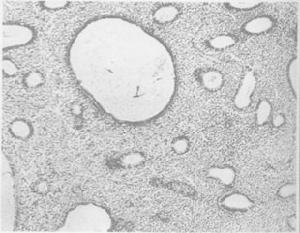

正常增生的子宮內膜現代醫學認為,機體受內外因素,如精神過度緊張、環境和氣候的改變、營養不良或代謝紊亂等影響,可通過大腦皮層,干擾下丘腦—垂體—卵巢軸的相互調節和制約。這種關係失常時,突然地表現在卵巢功能的失調,從而影響子宮內膜,導致功能失調性子宮出血。中醫認為“腎主生殖”,“腎為生命之源”,“經本於腎”,功能失調性子宮出血多與腎有密切關係,並與肝脾及血瘀等也有一定聯繫。

(1)診斷性刮宮:為排除子宮內膜病變和達到止血目的,必須進行全面刮宮,搔刮整個官腔。診刮時應注意宮腔大小、形態,宮壁是否平滑,刮出物的性質和量。為了確定排卵或黃體功能,應在經前期或月經來潮6小時內刮宮;不規則流血者可隨時進行刮宮。子宮內膜病理檢查可見增生期變化或增生過長,無分泌期出現。